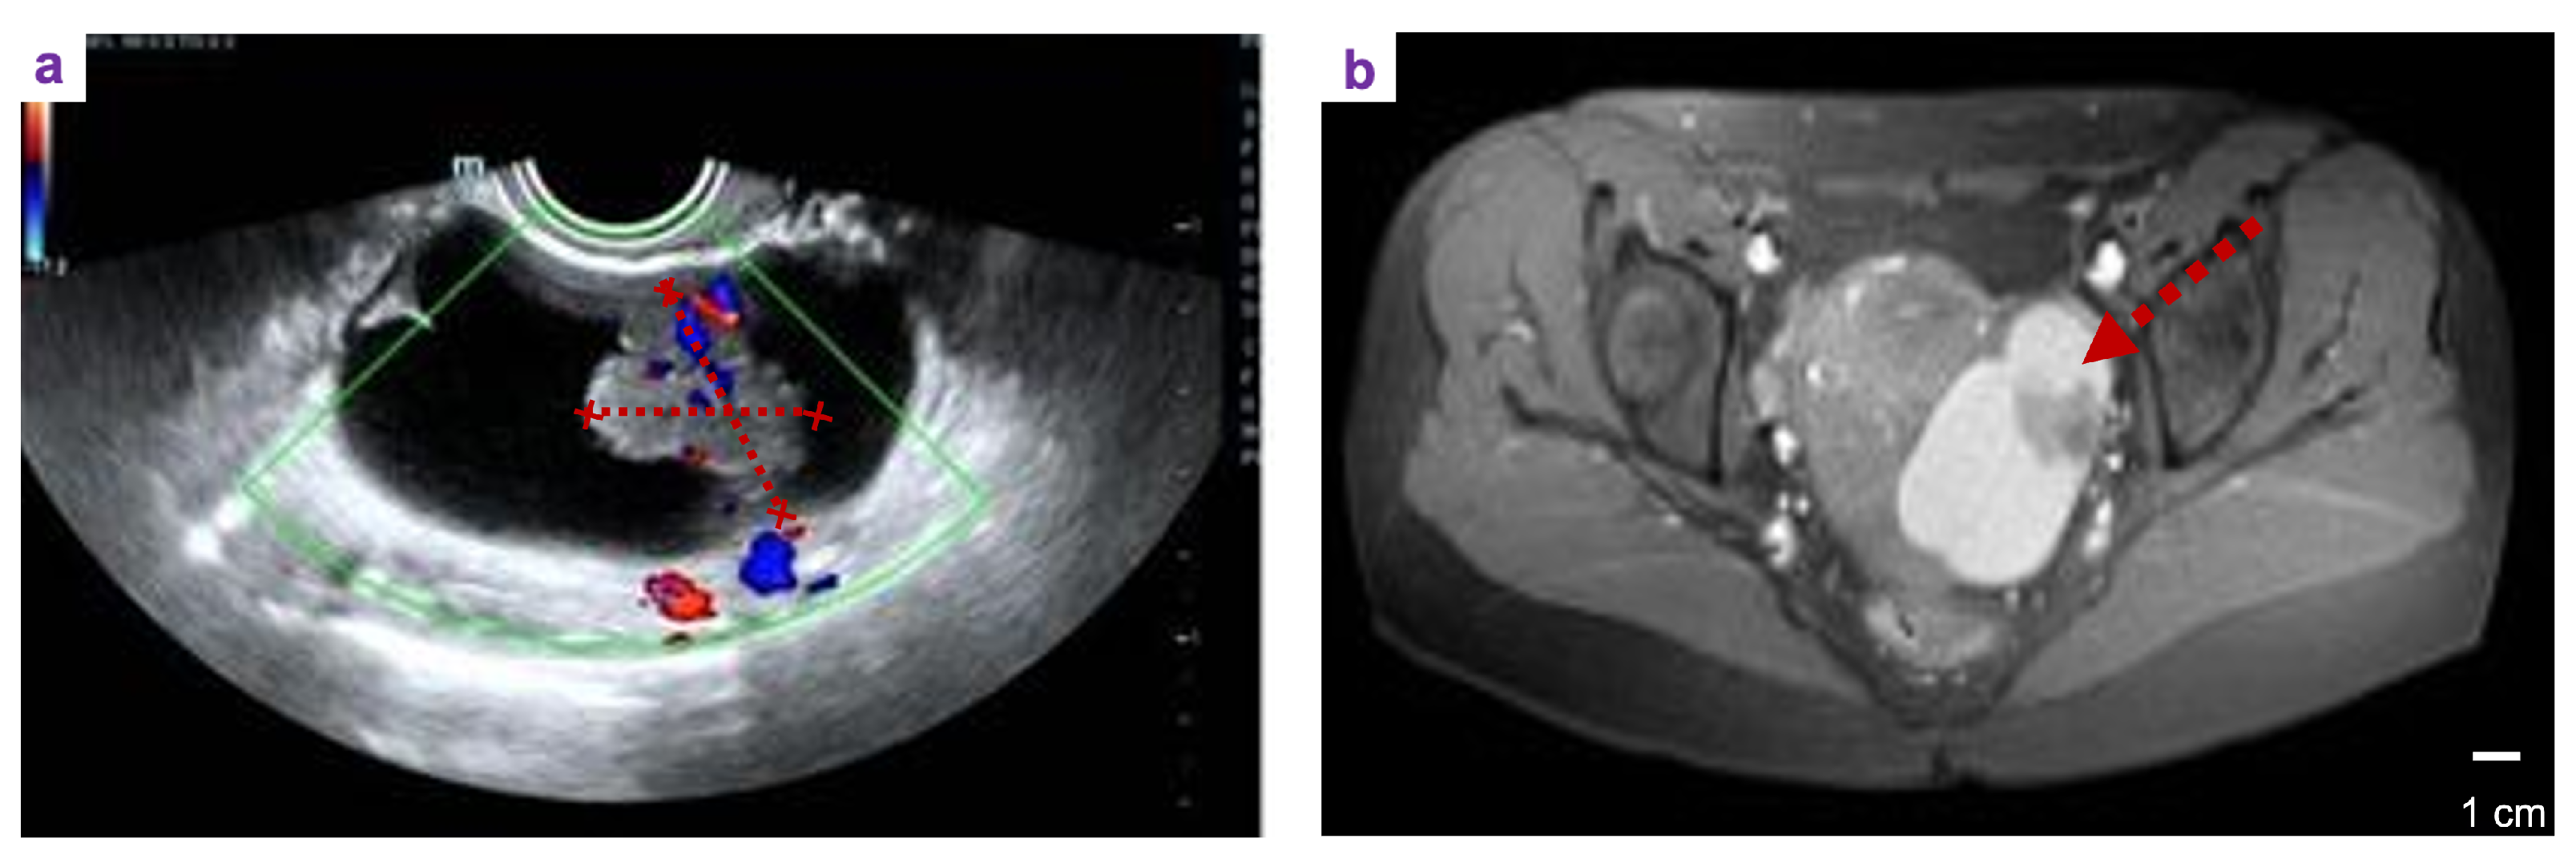

A 33 year-old female patient, unmarried, G0P0 came to the gynacological department with the main complaint of Left adnexal mass discovered on physical examination 7 days ago. She complained occasional mild lower-abdominal pain between menstruations, without bloating, weight loss, and abnormal vaginal bleeding. The past history did not show abnormalities. Her family history included her father suffered from hypertension and coronary heart disease, while her mother was healthy. At her first vist, a 7.5 × 4.4 cm mixed cystic-solid mass with nternal septations and vascularity was detected in her left adnexal region. (Figure 1a). Furthermore, the left adnexal cystic-solid lesion and small uterine fibroid was confirmed by MRI scan (Figure 1b). The laboratory result showd CA-125, CA-153, CA-199, HE4, CEA, AFP are all in normal range.

Figure 1. Image studies before fertility sparing operation. (a)transvaginal ultrasonography: a ; (b) Axial view of computed tomography of pelvis and abdomen (arrow) revealed the origin tumor location in right ovary.